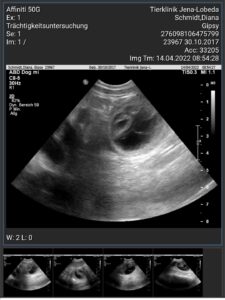

Ultraschalltermin: 14.04.2022

30. Tag 14.April 2022

Ultraschall Termin um 09:30 Uhr und jaaaaaa Gipsy ist trächtig

Wir sind überglücklich!!!!

Zu diesem Zeitpunkt sind die Fruchtanlagen so groß, dass sie i.d.R. gut sichtbar sind, aber noch zu klein, um die Anzahl der Fruchtanlagen zu bestimmen. Die Hündin kann zähflüssigen,

klaren bis milchig-trüben Schleim absondern, meist ein sicheres

Zeichen für eine Trächtigkeit.